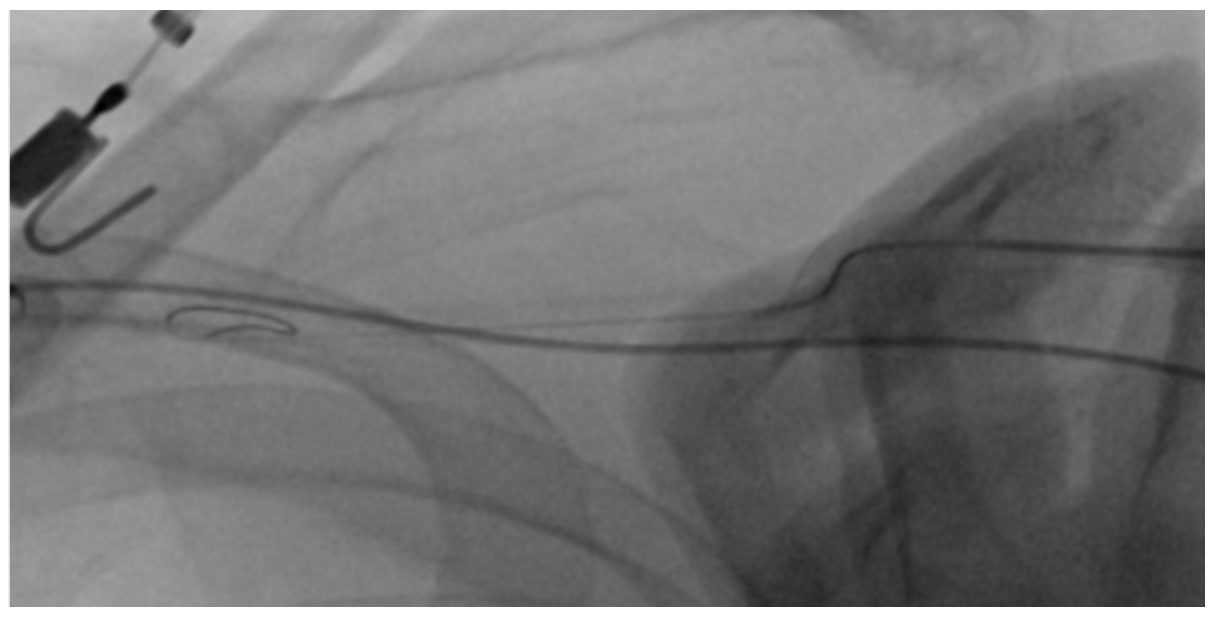

We then tried a 6 Fr Angio-Seal device (Terumo), but were unable to pass the inner part of the device with the collagen plug into the soft outer sheath which was kinked again at the indicated site (Figure 3). However, when we were retrieving the Angio-Seal, the foot plate was inadvertently trapped in the top part of the outer sheath. We maintained access after bypassing the caught foot plate with a needle introducer and wiring of the kinked outer sheath with an 0.018-inch Glidewire Advantage (Terumo) (Figure 4).